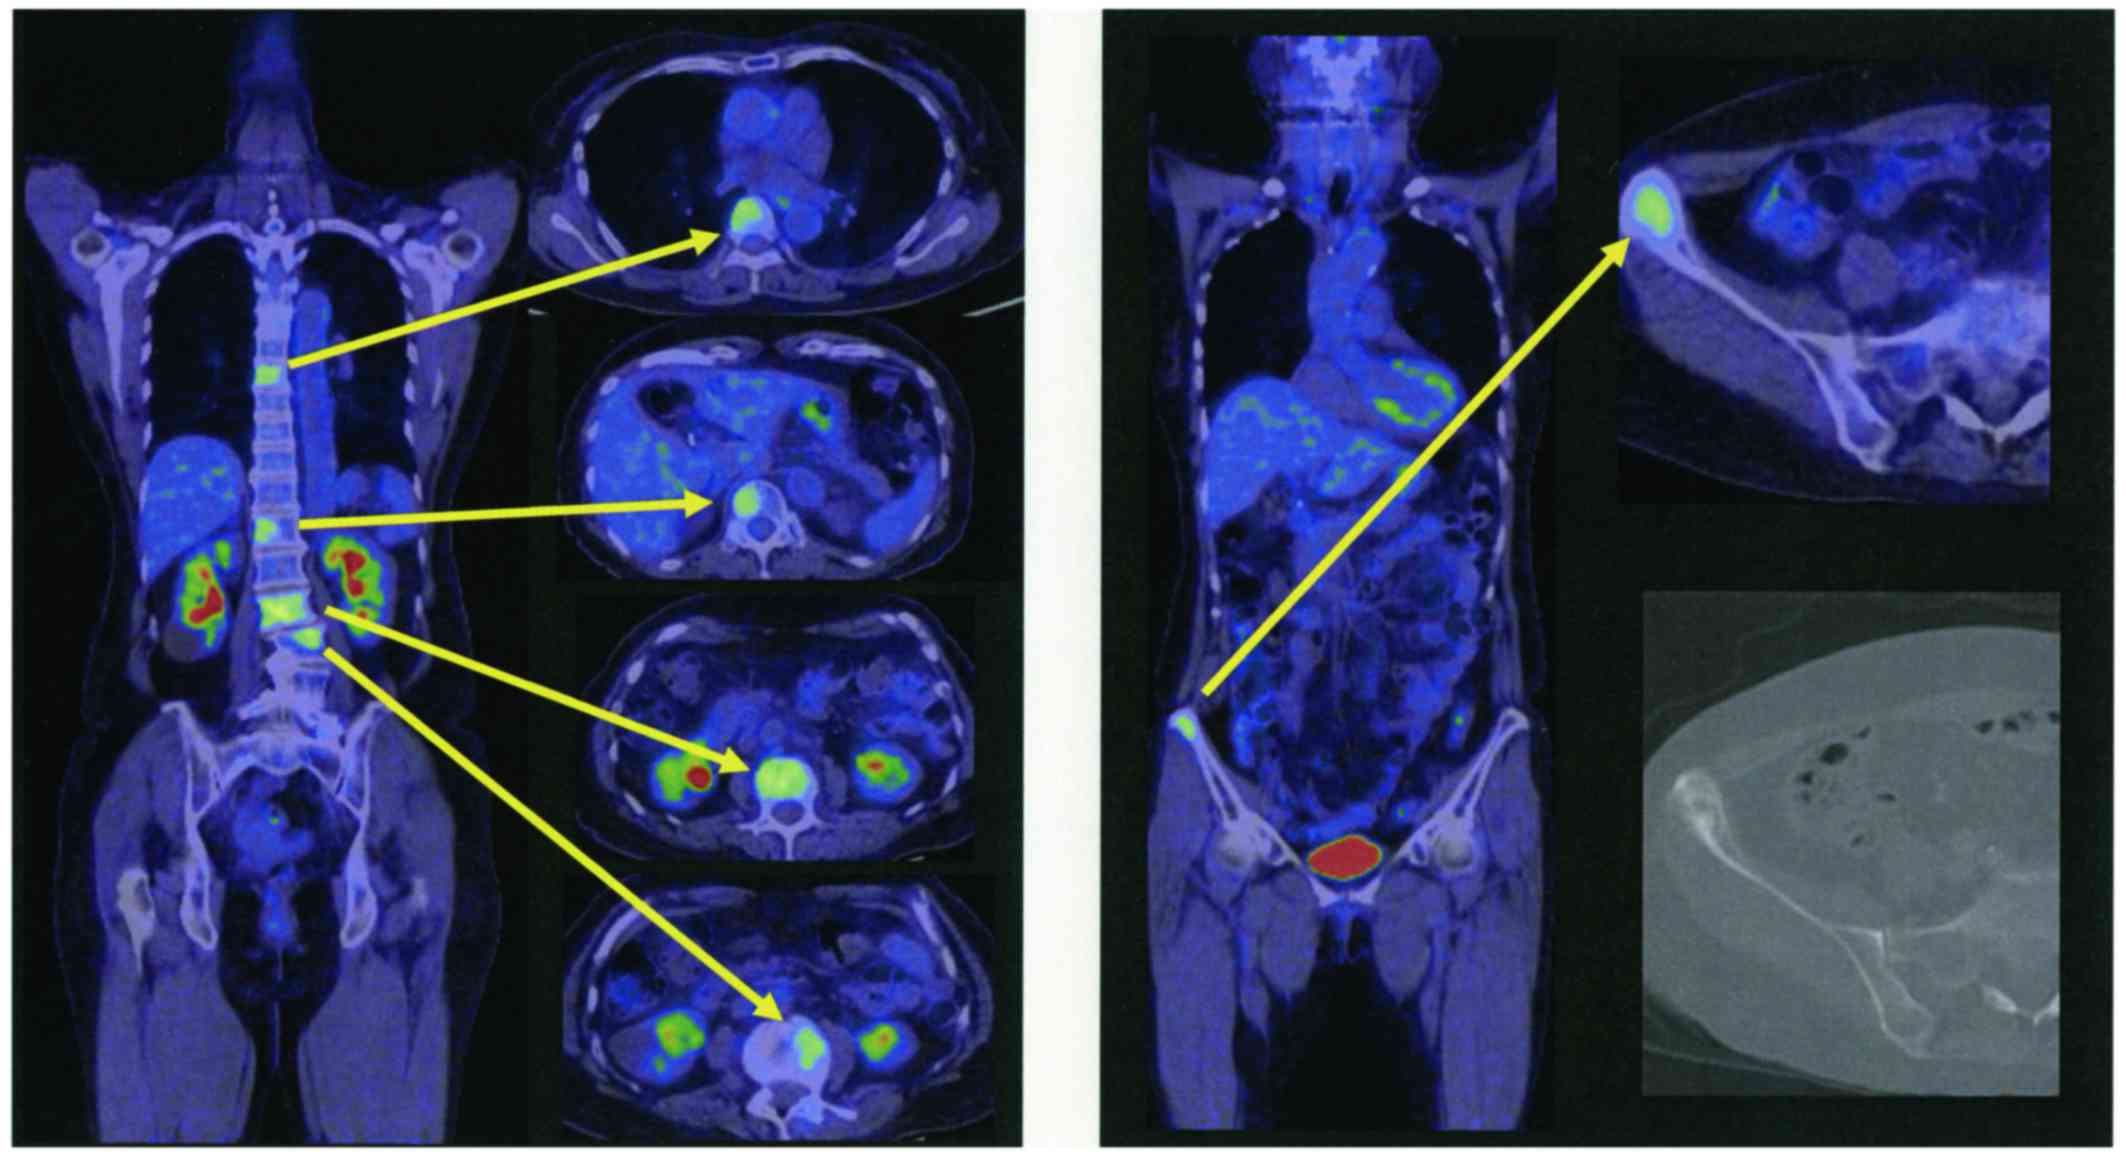

Intravenous hyperalimentation was initiated because the patient was unable to take meals due to poor performance status and nausea. The diagnosis of NSCLC with EGFR exon 19 deletion, resistance to erlotinib, the presence of CNS lesions and the poor performance status of the patient predicted a poor response to therapy with first-generation EGFR-TKIs. The patient was then treated only with best supportive care. In addition, positron emission tomography CT (PET/CT) images from a previous hospital (Fig. 2) revealed several metastatic hot spots in vertebra (Th7, 12, L2, 3, 5) and right ilium. Because the patient and her relatives preferred tumor-reductive therapy rather than palliative treatment, we performed liquid biopsy using plasma and cerebrospinal fluid (CSF) and tissue biopsy from the right ilium on day 6 after admission to rule out EGFR-T790M-related TKI resistance. The biopsy specimen analysis for EGFR mutation performed by peptide nucleic acid-locked nucleic acid polymerase chain reaction clamp was negative for all mutations in plasma samples, positive for exon 19 deletion and for exon 21 mutation but negative for T790M mutation in CSF samples. Cobas test (Cobas EGFR Mutation Test, version 2) performed using CSF samples was positive for exon 19 deletion, but negative for exon 21 and T790M mutations. However, Cobas test performed using tissue from the right ilium was positive for exon 19 deletion, negative for exon 21 mutation but positive for T790M mutation.

Figure 2.

PET and CT study. Bone metastases were evident in both PET and CT studies.

Based on these findings, therapy with osimertinib was initiated on day 9 after admission. Adverse effects including diarrhea, rash, dry skin or tiredness were absent and appetite was significantly increased. There was no hematological toxicity and a magnetic resonance image examination revealed no progression of central nervous system lesions, chest CT showed no drug-induced pneumonia and her performance status gradually improved to grade 2. She was discharged from the hospital. On day 20 of osimertinib therapy, the PET/CT examination revealed remission of bone metastasis with undetectable lesions (Fig. 3). Oral administration of osimertinib was continued and the patient clinical course was followed up in the outpatient department. After 2 months of therapy, MRI and CT images showed no disease lesions and the plasma CEA was gradually decreasing.